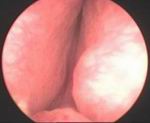

Prostatic enlargement is a comman problem is old age. By TURP nearly all patient who requires surgery for prostate can be treated successfully without any incision. Under anesthesia per urethral scope is inserted & under vision prostate is resected. Patient requires 2 to 4 days hospitalization & 1 week rest. Usually patient does not requires blood transfusion & patient can tolerate endoscopic surgery very well without risk of incontinance of urine.